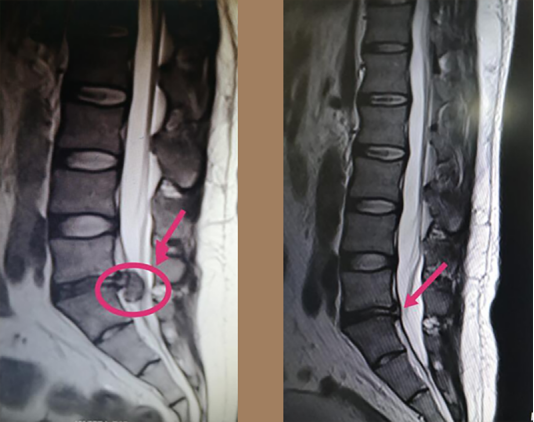

治疗前后影像对比图